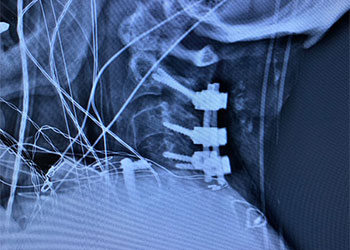

Surgical resection was felt to be most appropriate given the extensive size not being amenable to radiation, degree of symptomatic mass effect, favorable accessibility and non-eloquent location, and histopathologic diagnosis. He underwent a right frontal craniotomy, performed by Dr. Xavier Gaudin, with a three-quarter bicoronal flap for resection of both the sub frontal and superior subcortical masses. Grossly, the masses appeared so, friable, purple, and gray in appearance with a disncve plane from the parenchyma. Pathology was consistent with poorly differentiated adenocarcinoma from lung origin.